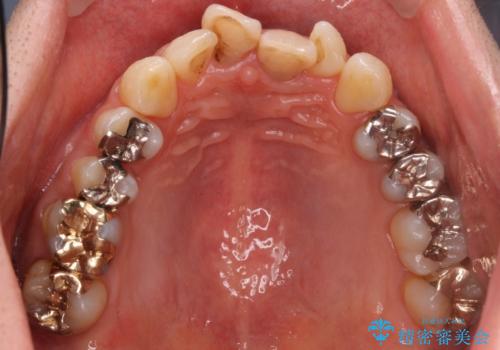

- 左上567:仮歯11,000円×3本、ジルコニアクラウン(スタンダード):121,000円×3本 合計396,000円費用は治療当時の料金となります

ブリッジでの修復は、抜歯後に歯がなくて噛みにくい期間が一切ありません。

歯茎の状態も良く、適合の良いブリッジを装着することができました。